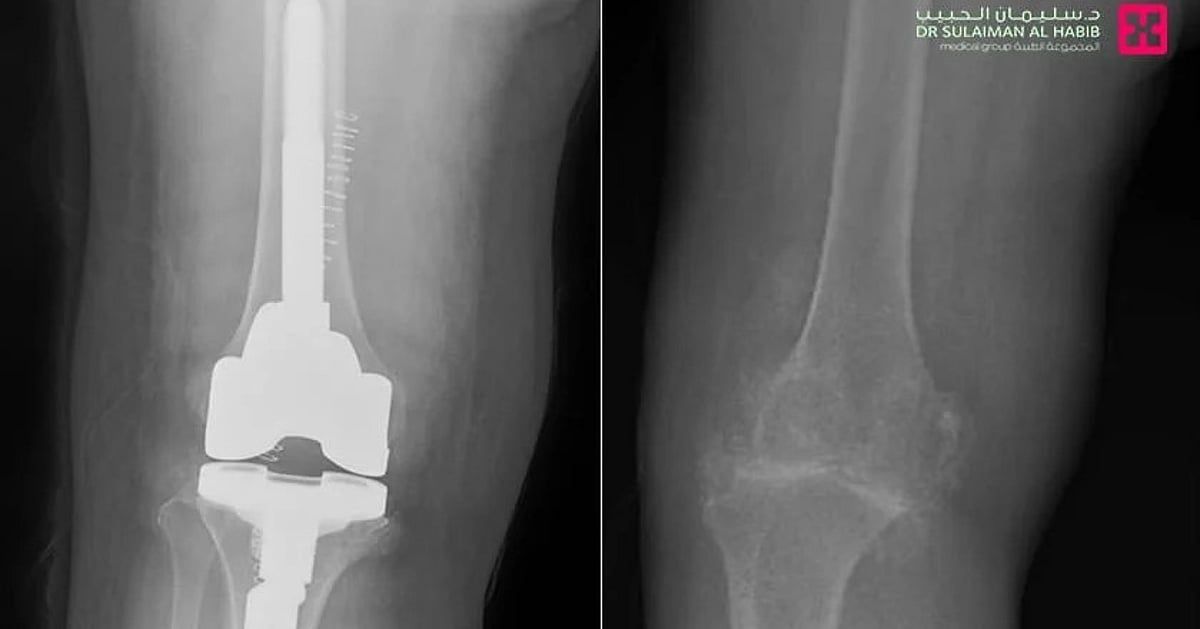

وقال د. حمد الشهراني استشاري جراحة العظام والمفاصل الصناعية، والطب الرياضي، رئيس الفريق الطبي المعالج، أن المراجعة جاءت إلى المستشفى على كرسي متحرك، مشتكية من عدم القدرة على المشي، وآلام حادة وتورم وتشوه في مفصل الركبتين، بالإضافة إلى تيبس وصعوبة في ثني الركبة، وخضعت لفحوصات طبية دقيقة، حيث أكدت صور الأشعة الطبية، وجود خشونة حادة بمفصل الركبة، مع تآكل بالعظم وارتخاء الغضاريف التي تحيط به وتحميه من الاحتكاك بشكل مباشر، وسبب كل ذلك في عدم قدرتها على الحركة وتقوساً بالركبة، وتمت مناقشة الحالة وفق معطيات التشخيص من قبل الفريق الطبي، ووضع خطة علاجية متكاملة، وأجريت لها عملية استبدال مفصل، في تدخل طبي استمر لنحو "90" دقيقة وقد تكللت ولله الحمد بالنجاح، وتم تحويلها مباشرة إلى جناح التنويم، حيث أمضت "4" أيام محاطة بالعناية الطبية الحثيثة، وبدأت في المشي على قدميها بعد العملية بساعات، وواصلت خلال تنويمها العلاج بالأدوية، بالإضافة إلى تنفيذها لبرنامج علاج طبيعي متكامل، وتحسنت حالتها الصحية باضطراد، إلى أن غادرت المستشفى وهي بصحة جيدة، حيث زال التقوس واستعاد الساق شكله الطبيعي، كما أنها تخلصت من الآلام وغيرها من الأعراض الحادة، التي كانت تنغص حياتها، إضافة إلى أنها استعادت قدرتها الكاملة على الحركة، حيث غادرت المستشفى إلى منزلها مشياً على قدميها وبحالة نفسية ممتازة.